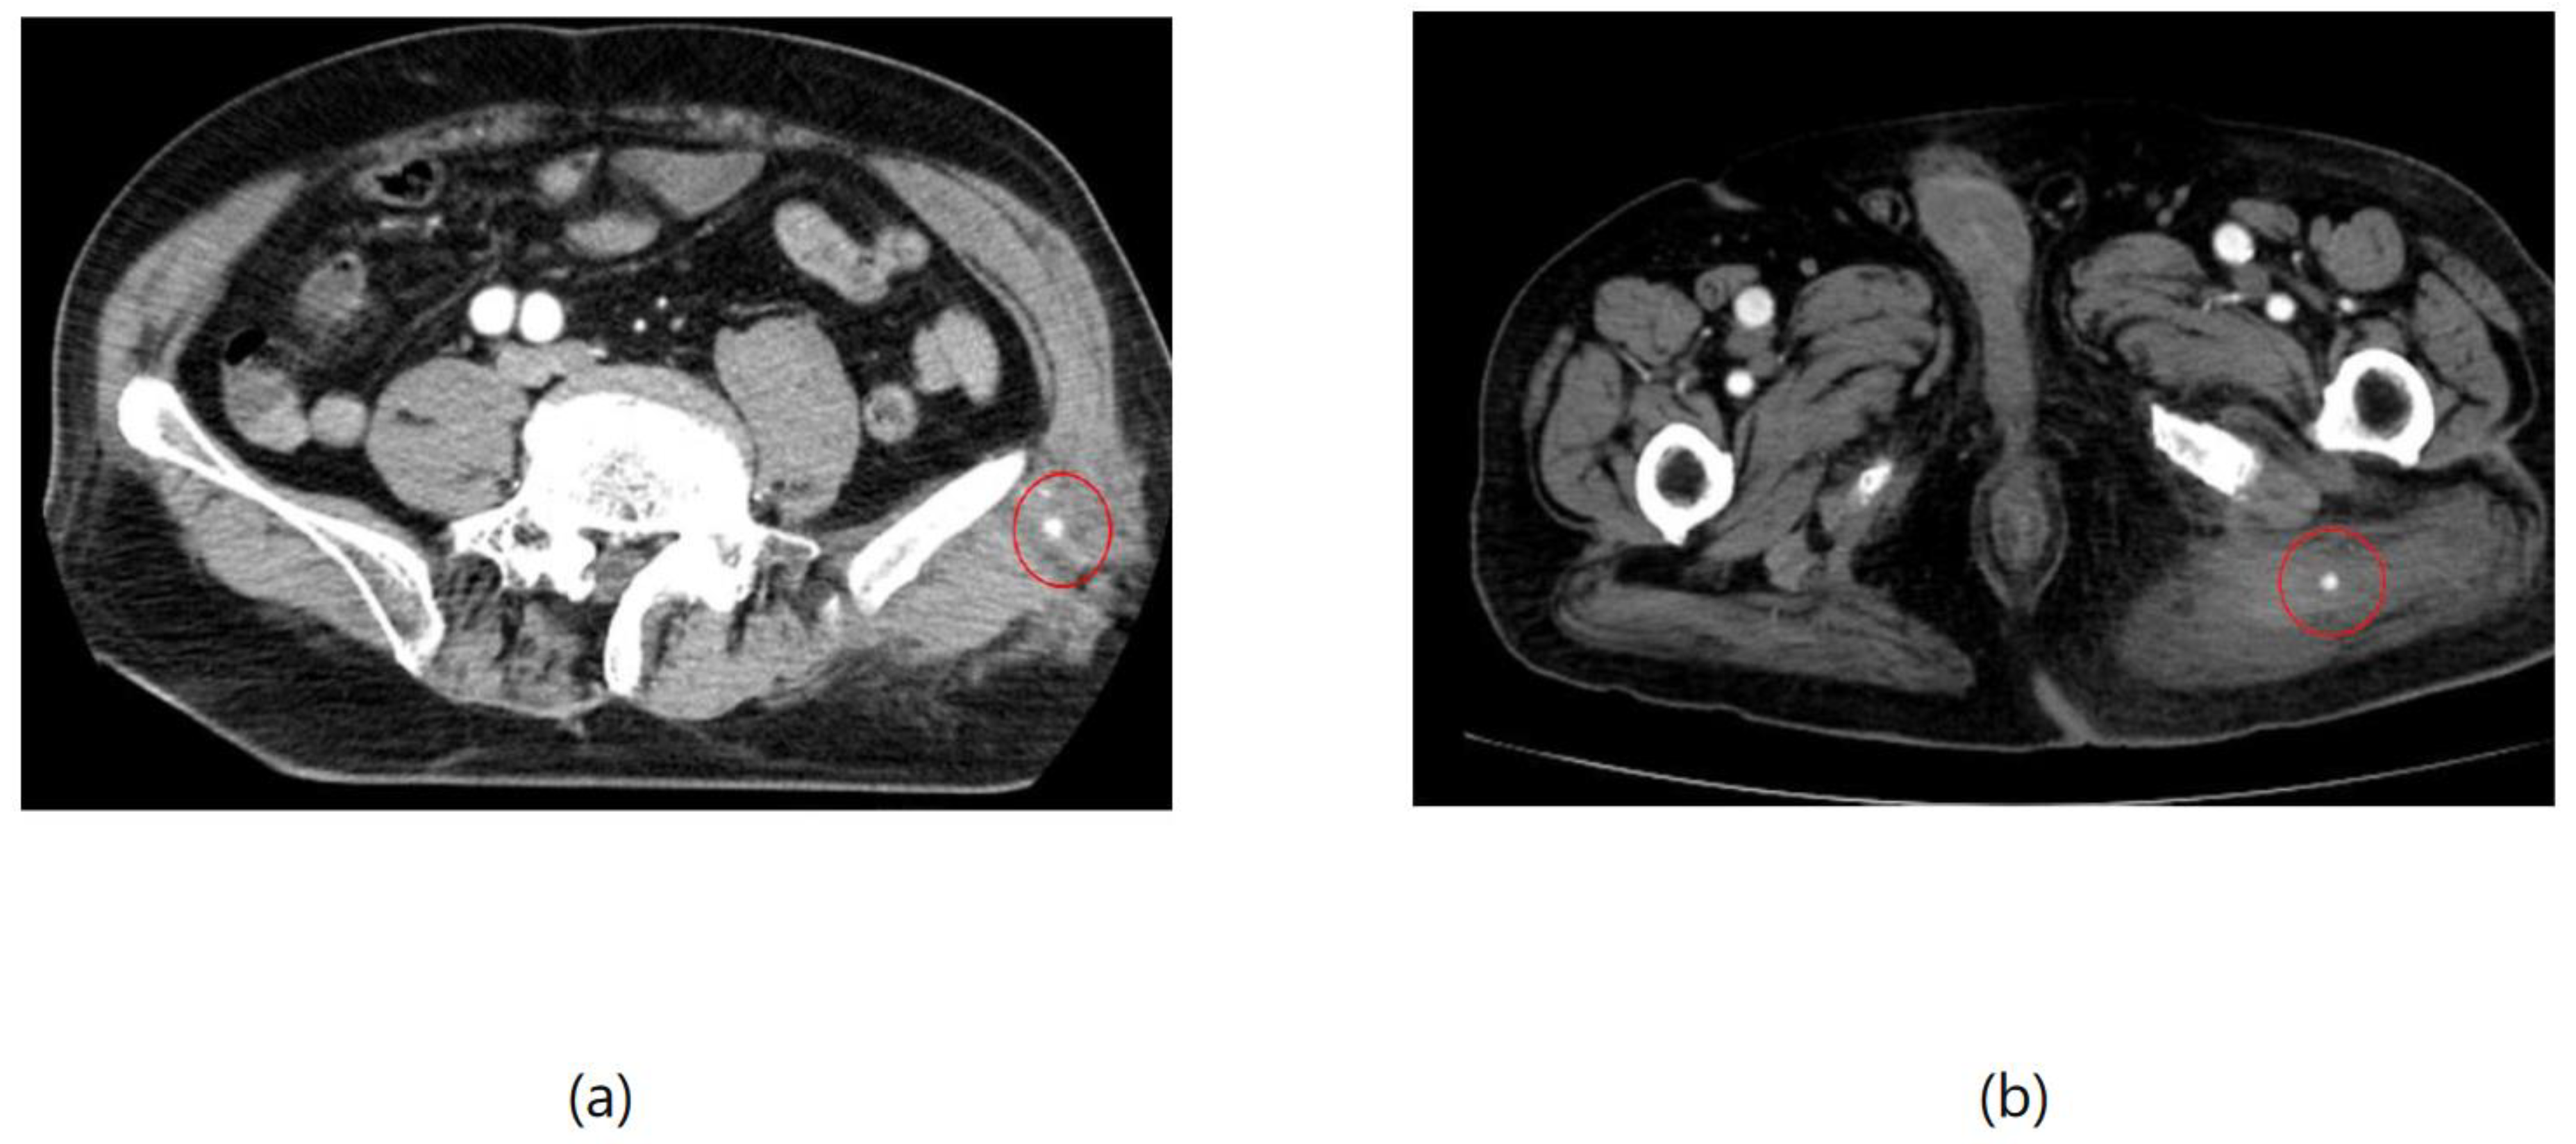

As an example, Figure 1 shows extravasation, or bleeding, from a polycystic kidney. Identifying the precise bleeding site on the computed tomography (CT) image presented a challenge. However, upon reviewing the angiography findings, it became evident that the bleeding originated from the area depicted in the CT image. In Figure 2, two instances of extravasation are depicted marked with the circles. Firstly, (a) displays a pseudoaneurysm visible post-spleen injury. Secondly, (b) illustrates a muscle hematoma in the chest region. In Figure 3, two cases of extravasation are evident. In (a), circles mark extravasation on a fractured pelvic region, indicating a significant injury. Meanwhile, (b) showcases an intragluteal hematoma, highlighting the varied presentations of extravasation across different anatomical contexts. These CT images provide valuable insights into the varied presentations of extravasation across different anatomical contexts.